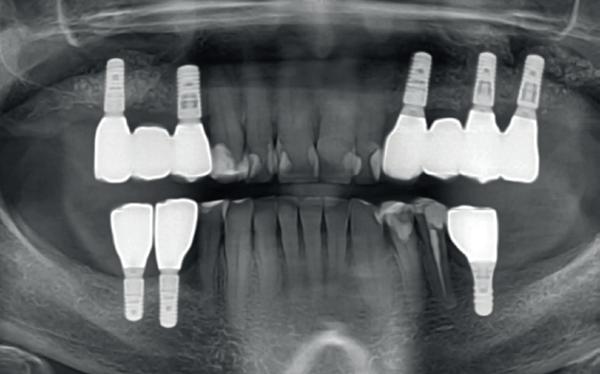

De (kunst)fouten van het immediaat implanteren

Immediaat implanteren, er zijn implantologen in Nederland die hebben geroepen dat het een kunstfout is om het niet te doen. Maar is dat nu wel zo? Wie vraagt er eigenlijk om deze procedure? Wat weten we eigenlijk van de langetermijnresultaten? Gebruiken we dezelfde soorten implantaten? Moeten we nog onderscheid maken tussen het front en de molaarstreek?

Gelukkig kan implantologie dan uitkomsten bieden. We extraheren een element, verwijderen granulatieweefsel, preserveren al dan niet de socket, plaatsen een implantaat en vervolgens een suprastructuur. Helaas kost dat genezingstijd. Na extractie vaak 2-3 maanden en na plaatsen van het implantaat (afhankelijk van een socket preservatie of botopbouw) wederom 3-6 maanden. Al met al voor een standaard (pre)molaar, van extractie tot plaatsen van de suprastructuur, zo’n 6 maanden. En dat doen we al meer dan 30 jaar met grote successen. Hoewel een implantaat gedragen oplossing vele nadelen kent op lange termijn, zien we dit toch als een van de meest betrouwbare behandelopties. En dat willen we als tandarts en patiënt graag: een duurzame oplossing die weinig langetermijncomplicaties heeft én geeft.

Vanuit de industrie is er al jaren een push gaande om dit proces te versnellen. We willen het blijkbaar sneller dan dat we dat nu doen. Een one-stop shop bij voorkeur. Om die reden zijn de behandelconcepten verschoven in de afgelopen jaren naar meer immediaat implanteren. Soms zelfs immediaat restaureren. We extraheren een element, verwijderen granulatieweefsel en plaatsen het implantaat meteen in de extractie-alveole. Dat scheelt ons en de patiënt namelijk 3 maanden genezing. Dat is een halvering van

6 IMMEDIAAT IMPLANTEREN

de behandelprocedure! Er zijn zelfs implantologen in Nederland die hebben geroepen dat het een kunstfout is om het niet te doen.

Maar is dat nu wel zo? Wie vraagt er eigenlijk om deze procedure? Wat weten we eigenlijk van de langetermijnresultaten Gebruiken we dezelfde soorten implantaten? Moeten we nog onderscheid maken tussen het front en de molaarstreek?

In 2018 ben ik zelf ook gestart met deze manier van behandelen. Mijn ervaringen zijn zeker positief, maar ik zie ook inmiddels de beperkingen van een

dergelijk concept (Afbeeldingen 3a-3f ). Sterker nog, ik ben er bijna helemaal vanaf gestapt. Niet omdat de resultaten tegen vielen, maar juist omdat ik bovenstaande vragen ben gaan stellen.

3a-f. Casus met gemis om primair te kunnen sluiten na fors defect als gevolg van ankylotische elementen. Externe resorptie na trauma en terugplaatsing op 13-jarige leeftijd.

Om alle bovenstaande redenen plaats ik momenteel, bij voorkeur, geen implantaten meer immediaat. Natuurlijk zijn er wel uitzonderingen. Maar die zijn jaarlijks inmiddels op één hand te tellen. Dat betreft alleen frontelementen met tenminste 2 mm autoloog bot buccaal (minder dan 0.5 % van de casussen volgens Kan et al.). Uiteraard dan guided geplaatst met een tijdelijke kroon indirect vervaardigd (afbeelding 1c-1j).